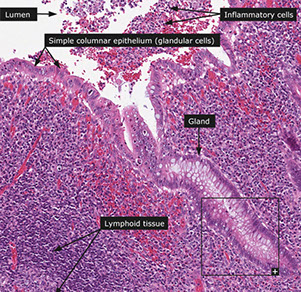

Histo similar to that of large bowel.

From lumen out: Mucosa, Submucosa, Muscularis externa, Serosa

Mucosa

Surface epithelium

- Columnar cells: eosinophilic cytoplasm and basally located nucleus. Includes absorptive cells and M cells

- Goblet cells: mucin droplet stains with PAS and Alcian blue. Seen more often in the crypts than in suface epithelium.

- M (Membranous) cells: Columnar, brush border, surround lymph aggregates to help bring in antigens. Can usually find lymphos between them.

--Usually fewer crypts between these M cells and lymph aggregates than in other parts of the appendix

-Crypts spread more unevenly than in colon. Work in cell renewal.

-- Endocrine cells: Flasked-  to spindle-shaped. May/not have luminal connection, respectively. (+) chromogranin stain. Found isolated/clustered throughout crypts

-- Paneth cells: abundant eosinophilic supranuclear granules. Found in crypt bases. Function unknown.

- Collagenous subepithelial BM. (+) PAS

-Lamina propria: made of collagen, fibroblasts, VANs, numerous lympho cells. Found in center of mucosa, though can be distorted by lymph aggregates.

-Lymph aggegates: absent at birth, peak in 1st decade then diminish. Similar to Peyer's patches in structure/function. though more cells in appendix have IgG than in colon.